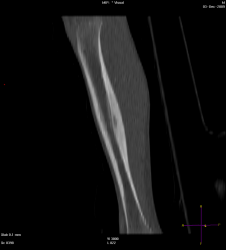

Мальчик 8 лет, был направлен травматологом к нам, с жалобами: на ноющую боль в голени в течении 2 мес., преимущественно усиливающася в ночное время, но проходящая после приёма НПВС. Провели МСКТ:

Думаю, что большого труда не составит определиться, что это за патологическое состояние, хоть и был отход от "классики". Случай ещё пока не верифицирован!

Остеоид-остеома. А в чем отход от классики?

Диф.ДЗ с первично-хроническим остеомиелитом.

Интересное наблюдение, но для "классики" остеоид - остеомы не хватает - пуговки - подобия секвестра в полости, но это в любом случае хронический остеомиелит подлежащий оперативному лечению.